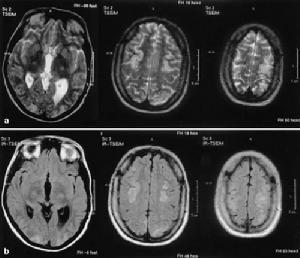

2.骨髓象紅系增生,可見類似病態造血表現在紫外線燈照射下骨髓有核紅細胞和外周血紅細胞因卟啉濃度增高呈現鮮紅色螢光。